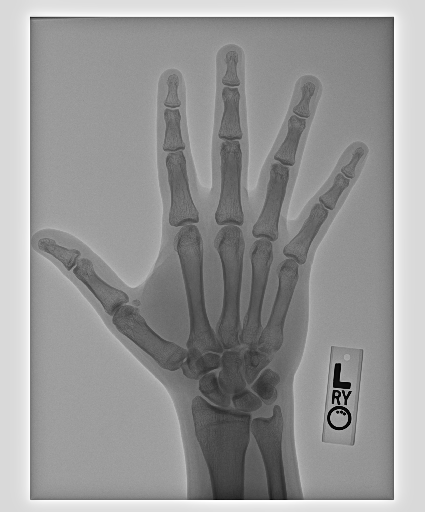

In this work, we focus on a subset of the MURA dataset [17] containing only hand images. In total, we have 5,543 images of 2,018 studies of 1,945 patients. Each study is labeled as negative or positive, where positive means that there was an anomaly diagnosed in this study. There are 521 positive studies, with a total of 1,484 images. Figure 1 shows some examples from the dataset. In summary, our contributions are as follows: